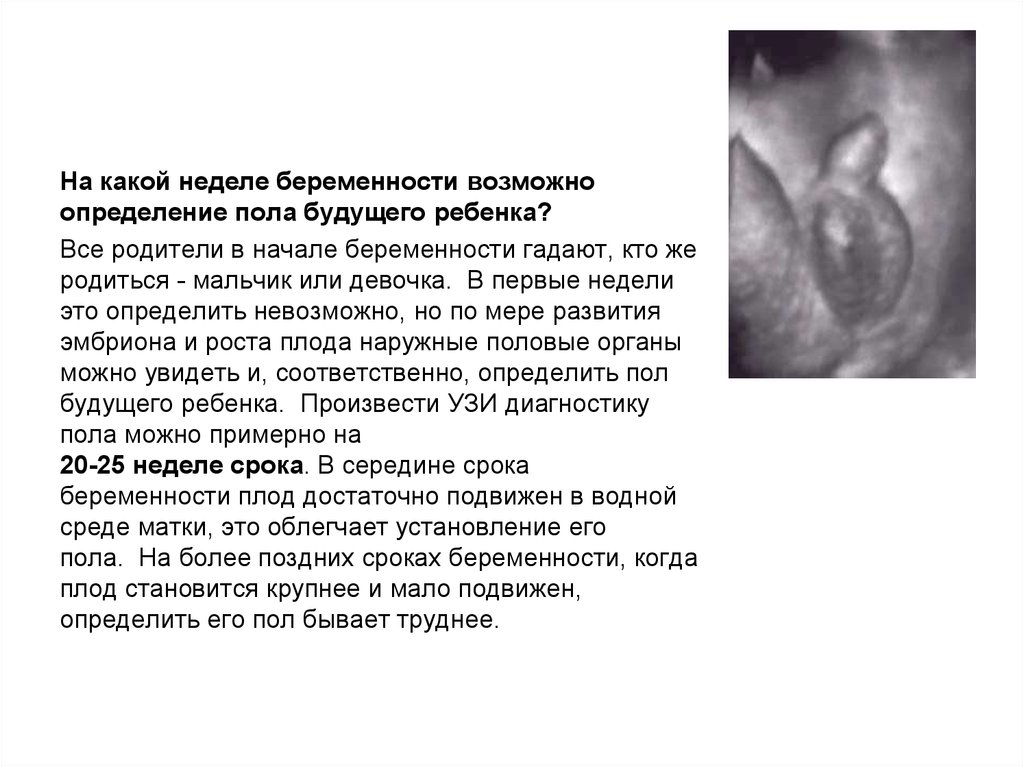

Пол на 14 неделе беременности по узи

Пол на 14 неделе беременности по узи 88 фото